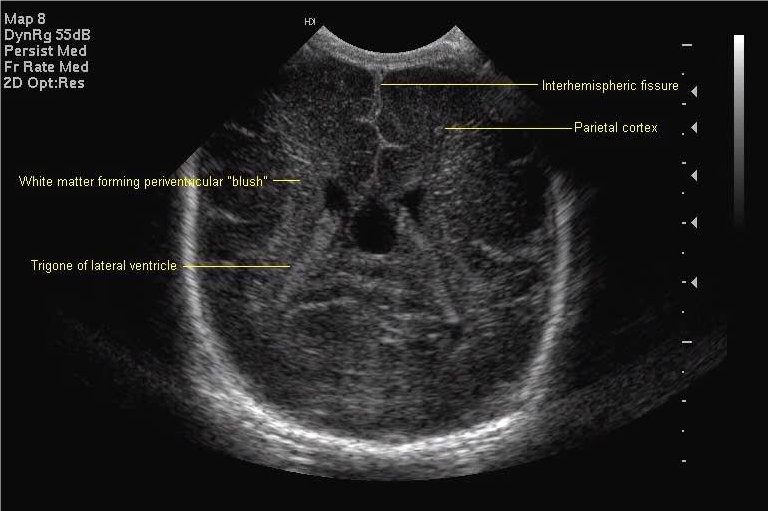

All scan results should be discussed with parents and, unless normal, this should be done by a member of the senior medical team. Although standard views for examination and hard copy print out are shown below, it is good practice to examine the peripheries of the brain including extreme lateral sagittal views, extreme anterior and posterior coronal views.

Posterior coronal